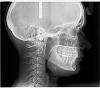

wel Опубликовано 13 марта, 2007 Поделиться Опубликовано 13 марта, 2007 Здравствуйте! У меня такая проблема: передние зубы до 5-к стоят с промежутками на обеих ч (наследственное от мамы). Кроме как психологического, никакого другого дискомфорта у меня до сих пор не было. Обратилась с консультацией к ортодонту. Выяснилось, что к тому же глубокий прикус. Рекомендуют брекеты (металлические или по моему выбору - эстетические) + накусочная площадка, ретенционный период и возможно еще виниры. Усечение уздечки тоже упоминалось. Направили на теленографию в боковой проекции. Вопросов много, буду рада даже если ответите на некоторые!Можно ли достигнуть желаемого рез-та только брекет системой? Совершенно не хочется лепить виниры на здоровые зубы из-за стирания эмали + окрашиваемость цемента и срока эксплуатации 10 лет (это если не будет сколов раньше…).Какие системы лучше, читала о Лингвальных брекетах и системе Damon 3. У мамы с возрастом щель между первыми резцами увеличивается, даже если мне сейчас все выровняют, не будет ли это временно, или ретейнеры мне пожизненно придется носить? Все зубы по высоте маленькие, особенно жевательные, не будет ли из-за этого проблемы с крепежом системы? Если знаете, посоветуйте специалиста в г Киеве? Ссылка на комментарий

wel Опубликовано 15 марта, 2007 Автор Поделиться Опубликовано 15 марта, 2007 Вобщем, вот что у меня вышло: Можно ли еще что-то добавить по моему вопросу? У Вас достаточно большие промежутки между зубами, после снятия брекетов требуется длительное ношение ретейнеров, не менее 10 лет. Иначе могут образовываться промежутки вновь. А что Вас смущает в несъемных ретейнерах? К ним быстро привыкают, они не доствляют дискомфорта. Только что заметила Ваш ответ! 10 лет... Не совсем знаю как они крепятся, почему-то кажется, что с ними нужен особый уход как с брекетами : чистка после каждого приема пищи и тд., иначе - КАРИЕС! Ссылка на комментарий